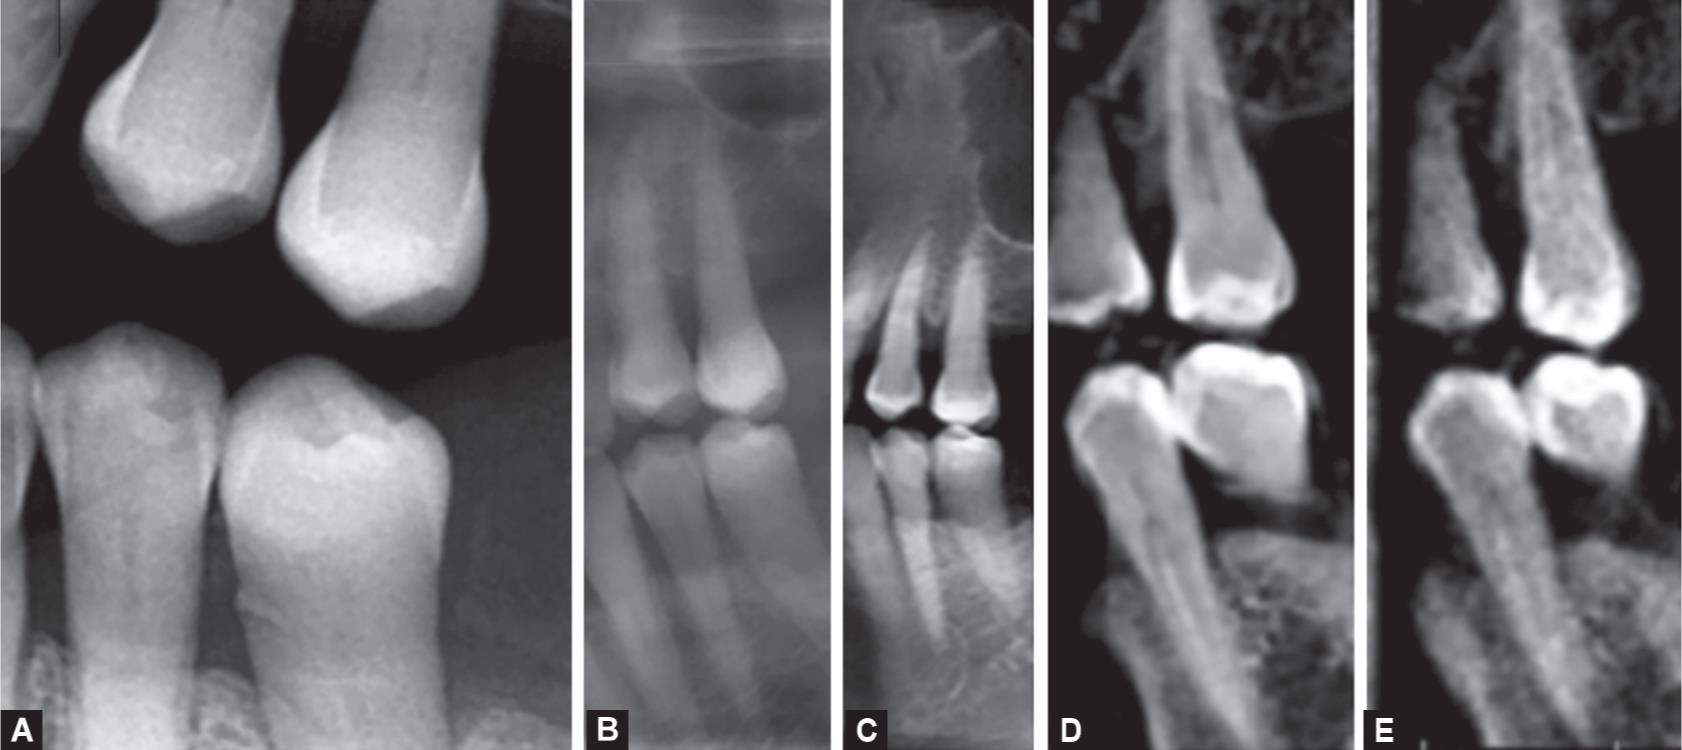

Examples of intraoral and extraoral bitewing radiographs. (a) Intraoral Extraoral Bitewings But does this unconventional type of There are many benefits to using extraoral bitewings in your dental or dental specialty practice. The development of specialized panoramic radiograph machine software has spawned the introduction of an innovative and promising dental radiographic examination type: To compare the diagnostic accuracy of digital intraoral and extraoral bitewing (eo bw) radiography in the. Everything you. Extraoral Bitewings.